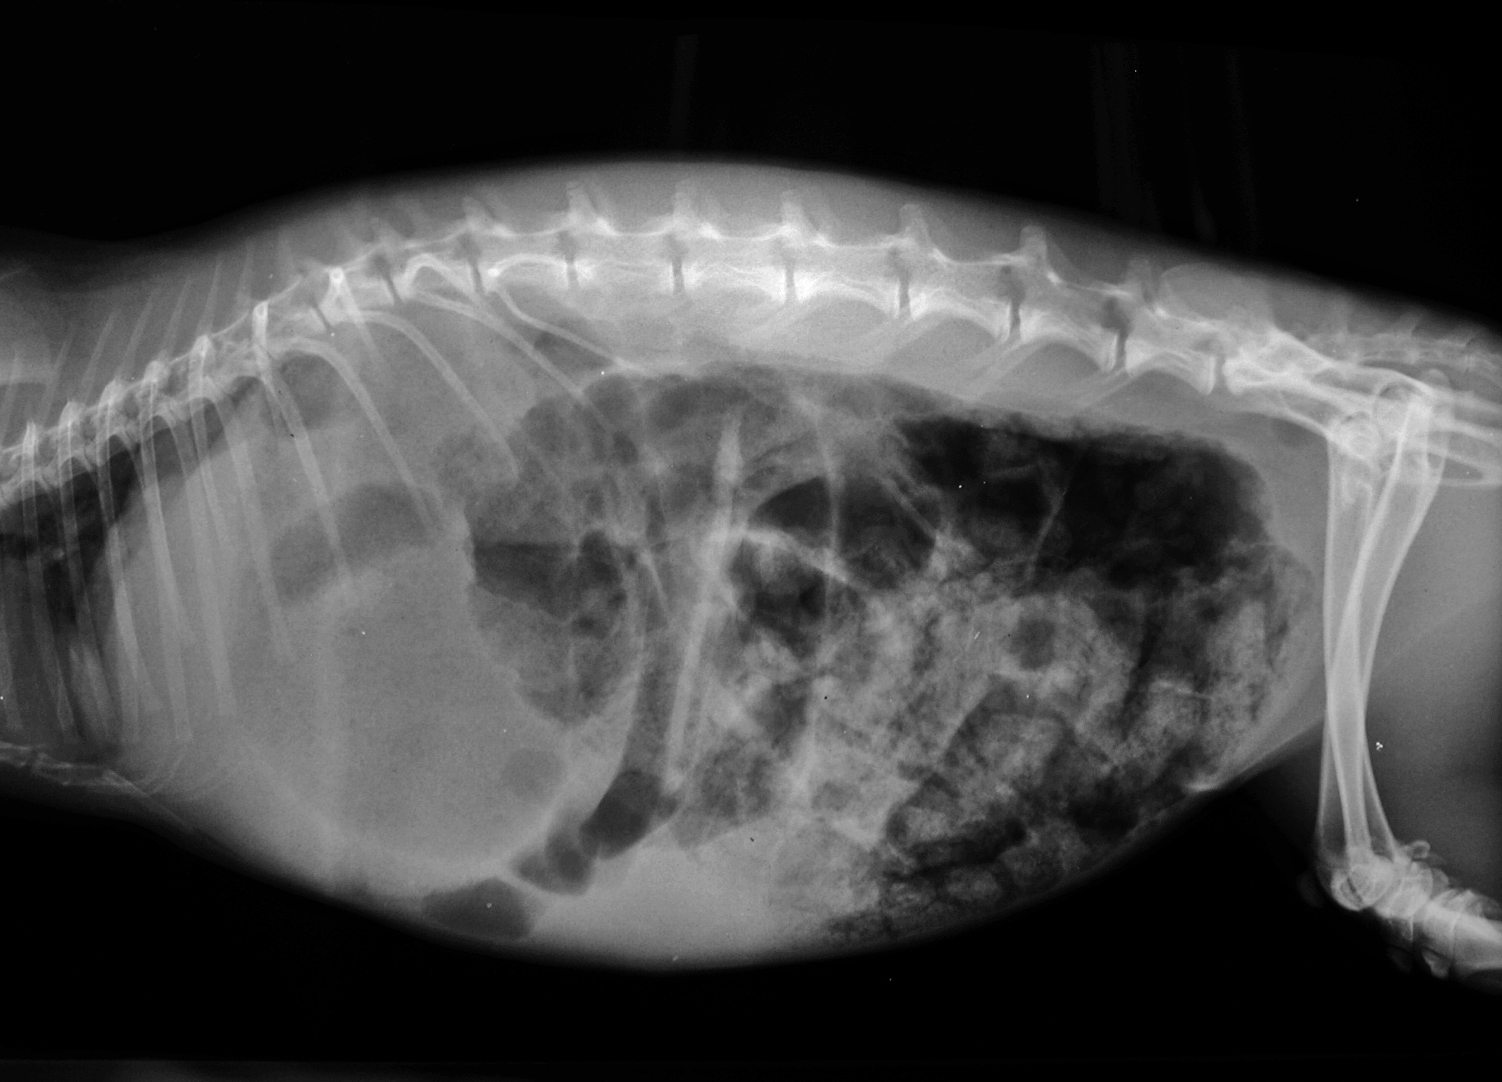

Mucoid enteropathy

Gastrointestinal disease